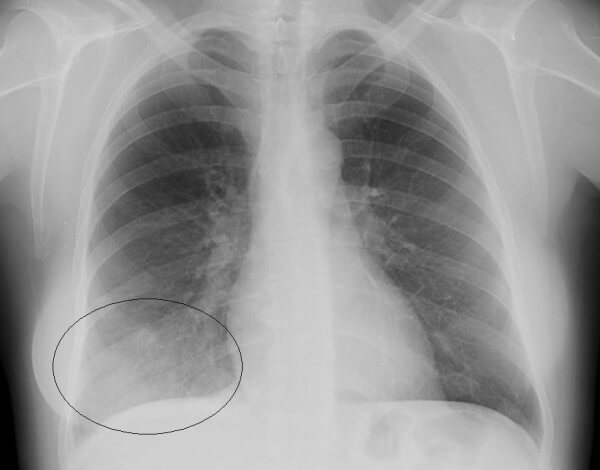

На снимках видно, что воспалительный процесс локализуется лобарно или сублобарно (то есть поражается доля легкого) с вовлечением плевры. Легочный рисунок при этом изменяется, а легочные корни расширяются. Видны застои жидкости в плевральной полости. С течением болезни тени на снимках становятся темнее.

Крупозная пневмония

- Крупозная пневмония. Наблюдаются изменения нормального легочного рисунка, жидкость в полости плевры, признаки инфильтрации одной из долей легкого, расширение корней. По мере развития воспалительного процесса выраженность изменений и интенсивность окраски затемнений усиливается.